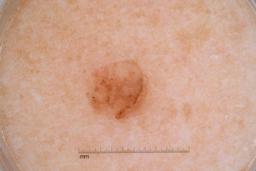

MSK-4

- Name: MSK-4

Description:

Images found based on a search for patients with a personal history, clinical diagnosis, or differential diagnosis of melanoma. All diagnoses confirmed by histopathology.